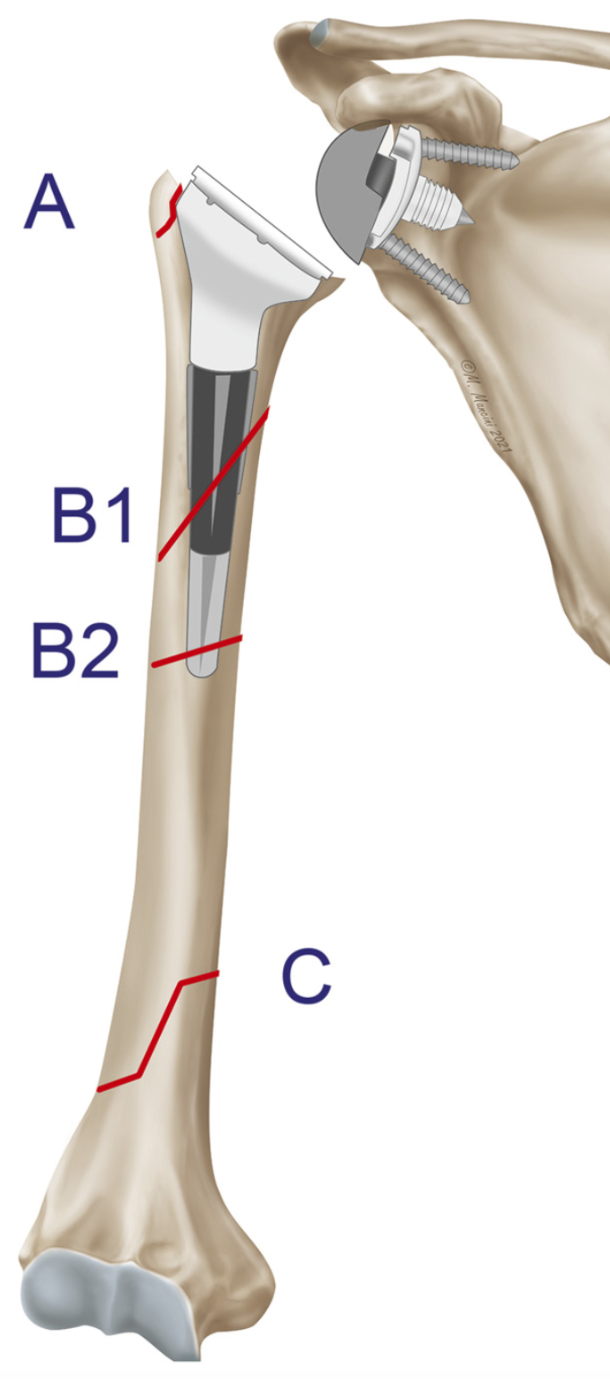

Alessandro Donà | Luigi Tarallo | Gian Mario Micheloni | Andrea Giorgini | Giuseppe Porcellini Introduction Periprosthetic shoulder infections have a reported incidence of 0.4